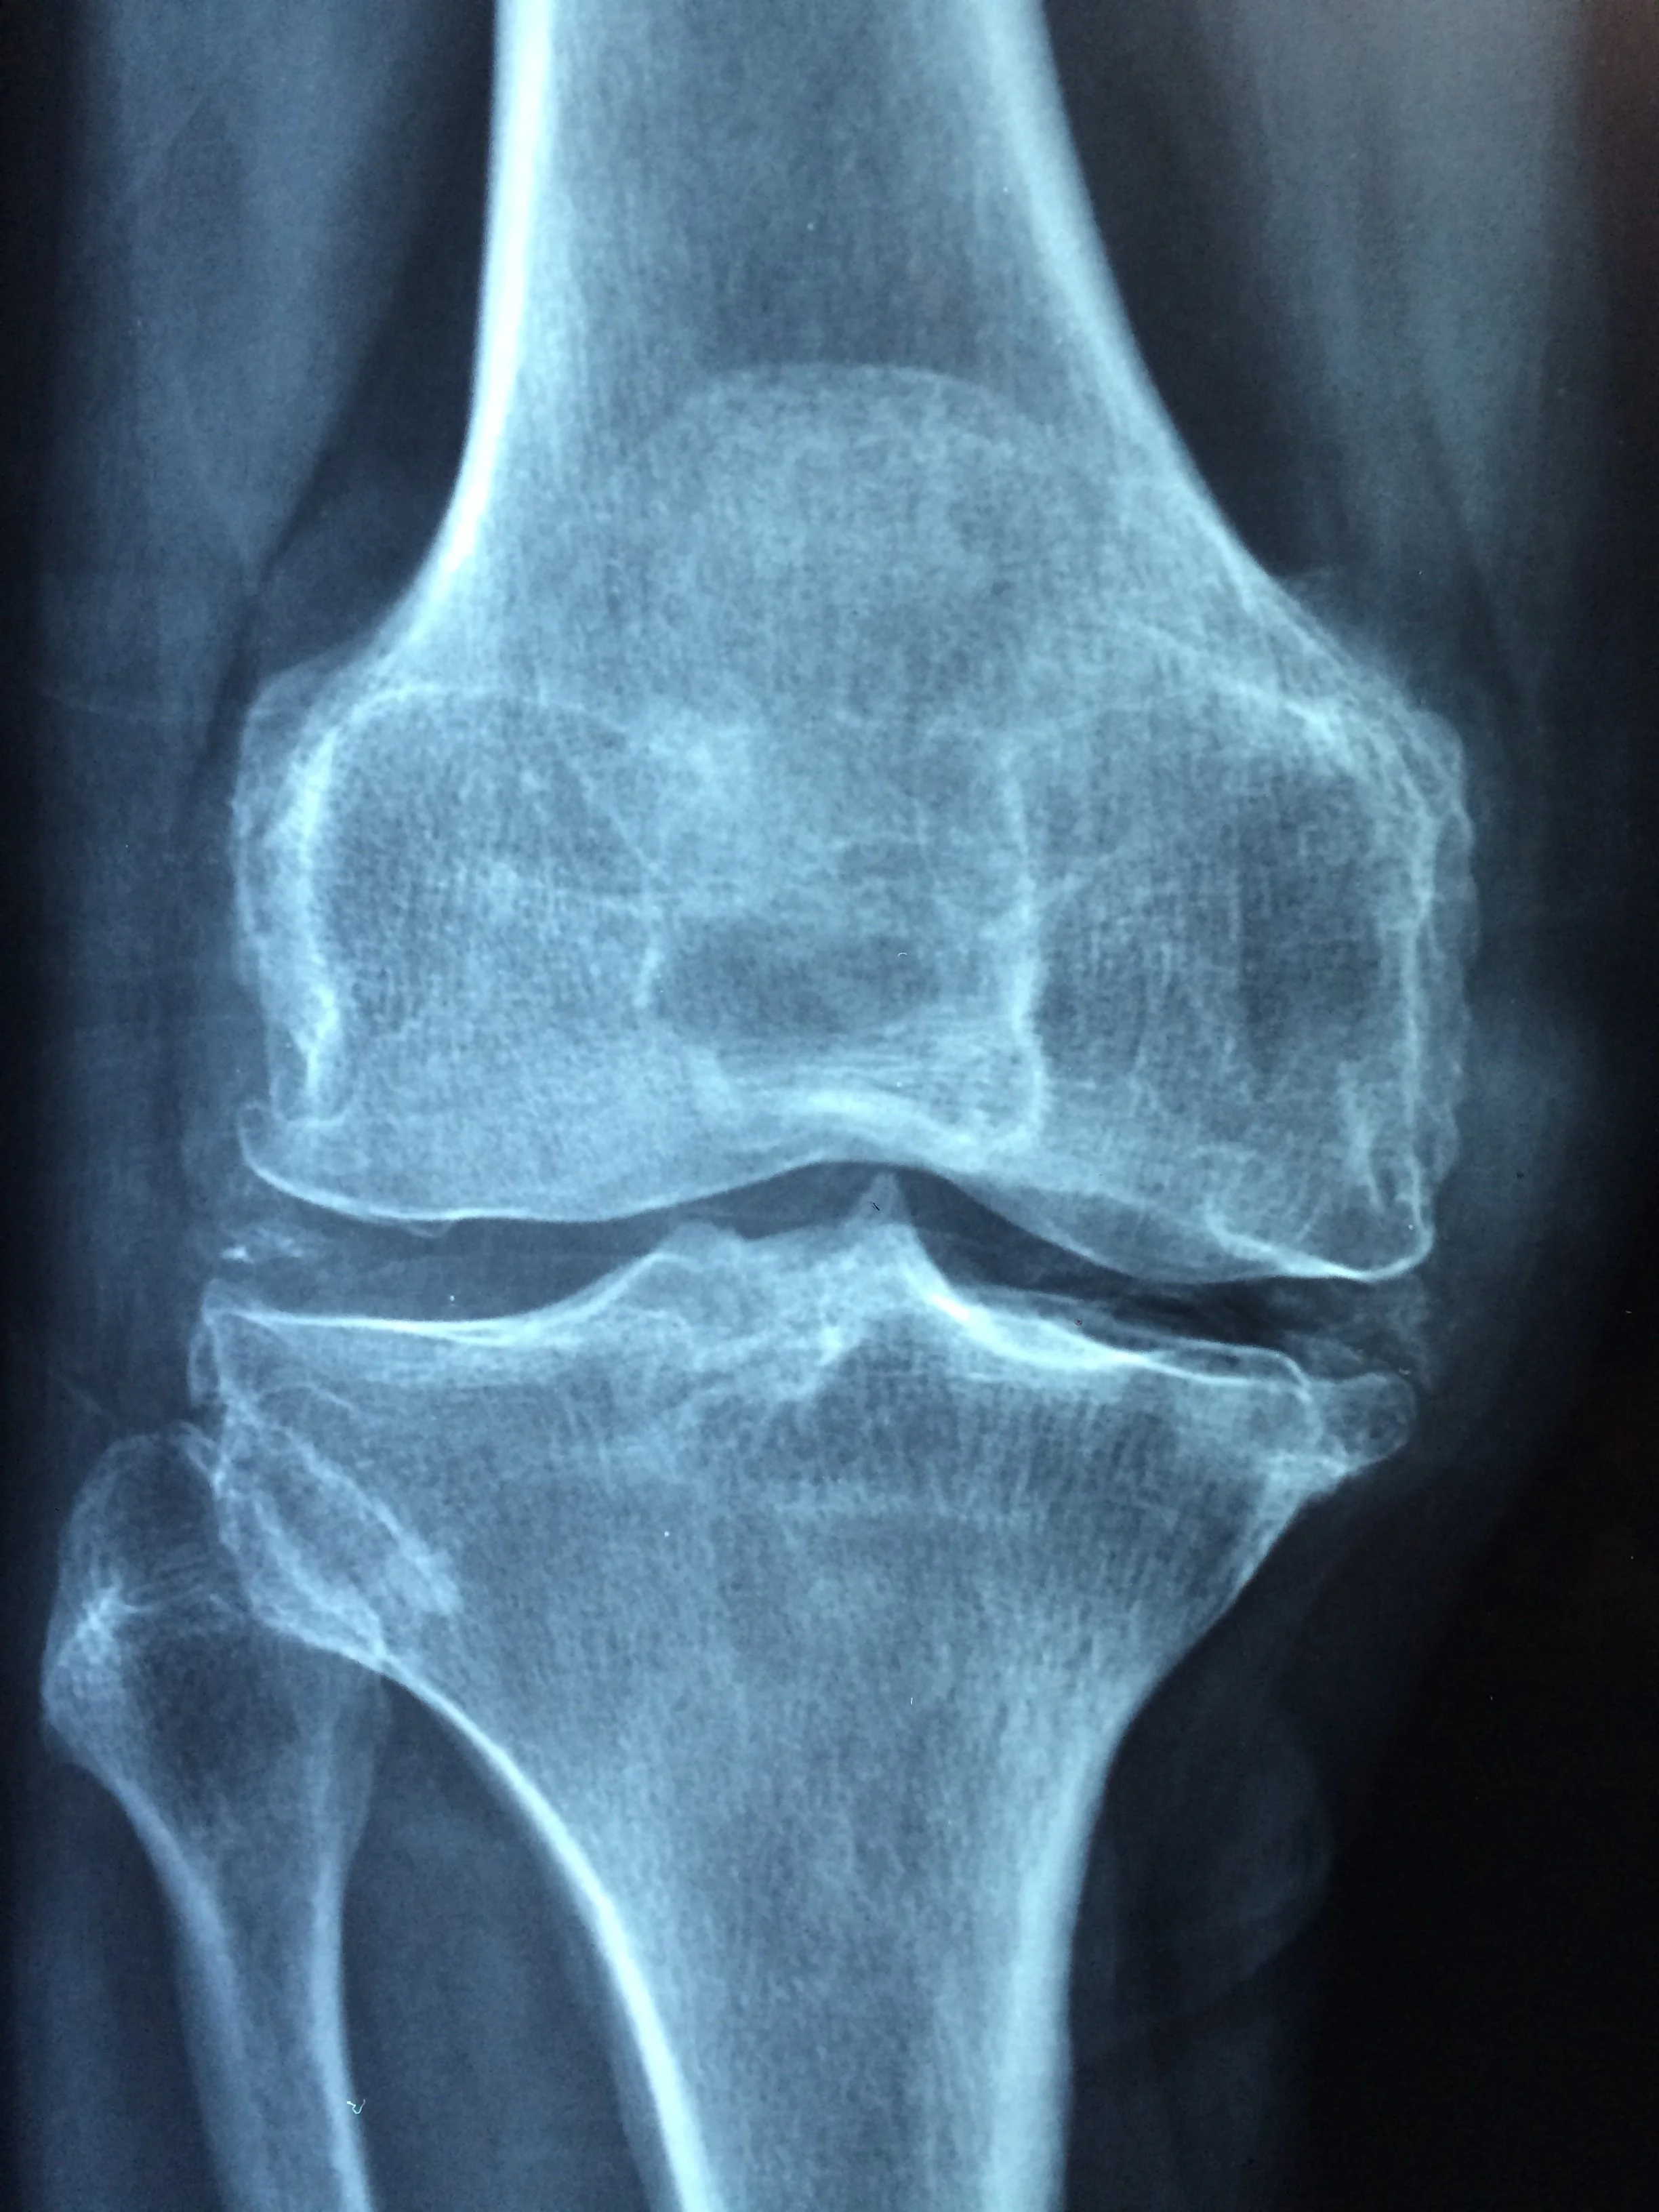

After my recent second knee surgery, I had an episode of hives. Nothing major. Nothing serious. Nothing contagious. At first I dismissed them. They appeared randomly. I thought it was stress. Then the pattern became clear. My body was signaling that I had pushed too hard, too soon. I had to listen.

When I first noticed the hives 10 weeks after surgery, I assumed I was overreacting. I assumed it would pass on its own. But data on recovery in older adults offers a cautionary note. Functional recovery after surgery in people over 60 can take months. And even though I was walking well, not taking medicine, my body needed more support and rest. For basic daily activities it may take three months or more to return to baseline. For more complex tasks the recovery period can extend longer. These timelines are a reminder that the body needs time and thoughtful care to rebuild strength.